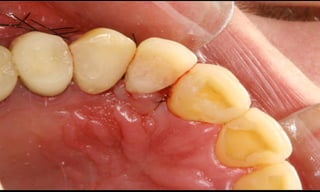

Baixo potencial para perda óssea marginal

(Tenenbaum et al. Impl Dent, 2003);

Resultados estéticos periimplantares otimizados

(Abboud, M. IJOMI, 2005).

10-10-2005

Novembro de 2005

24-01-2006

Cone Morse